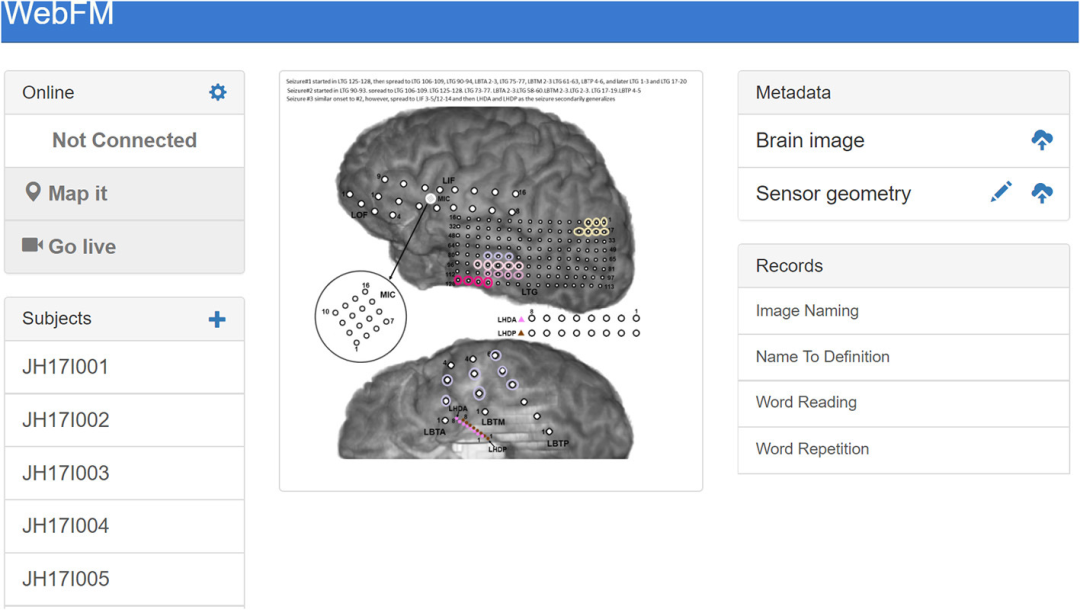

ESM的局限性激发了一种互补的映射技术,该技术基于对行为任务期间ECoG或立体EEG被动记录的功率谱(特别是在高频)中与任务相关的变化的估计。这种映射技术,以下简称ECoG功能映射,生成与任务相关的皮层激活地图,其中可能包括任务招募但对任务性能不重要的皮层。相比之下,ESM使用皮层功能的暂时电生理破坏来模拟组织切除的急性行为影响,并被认为特定于对任务表现至关重要的区域。尽管如此,一些临床研究表明,ECoG功能映射和ESM之间存在良好的对应关系。此外,几项研究表明,ECoG功能映射可用于预测切除后的神经损伤,在某些情况下,它预测了ESM没有预测的损伤。由于这些原因,一些癫痫手术中心已经开始使用ECoG功能映射作为ESM的补充,有时提供皮层功能的初步地图,以指导ESM的使用。然而,由于缺乏技术资源,特别是可用于临床脑电图监测系统的软件,大多数癫痫中心尚未采用ECoG功能映射。近年来开发了几个ECoG功能映射包。例如,SIGFRIED在校准块中获得了神经活动的大量基线分布,然后通过平均行为在时间块中引发的神经活动来快速积累皮层激活的估计值。一种名为cortiQ的商业产品能够执行这种基于块的映射范式,这使得训练有素的临床专业人员能够进行被动ECoG映射。(SIGFRIED和cortiQ都是使用BCI2000框架构建的)

笔者认为,仔细阅读这篇论文之后,其实不难想象出一种系统架构,其中用户的神经数据被发送到与服务器后端实时通信的浏览器应用程序,允许基于云的服务应用复杂的机器学习技术进行分析处理,更进一步,人们可以开发一个基于浏览器的应用程序,将多个用户的神经数据传输给彼此的客户,从而促进基于大脑的通信。由于专注于前端用户交互,许多软件包都是用JavaScript编写的,这些软件包支持交互式应用程序和可视化的快速实现。公共JavaScript API允许丰富的BCI交互,实验范式可以利用谷歌图像搜索等网络资源,在运行时提供各种量身定制的刺激。跨设备兼容性是将浏览器用作可视化和刺激演示平台的另一个优势。任何支持浏览器的设备(智能手机、平板电脑、PC甚至游戏机)都可以用于呈现刺激或可视化输出。由于这种“写完代码就能运行”的开发过程,临床医生可以使用WebFM从患者房间外的智能手机上实时查看映射结果,而ECoG功能映射由技术人员运行。